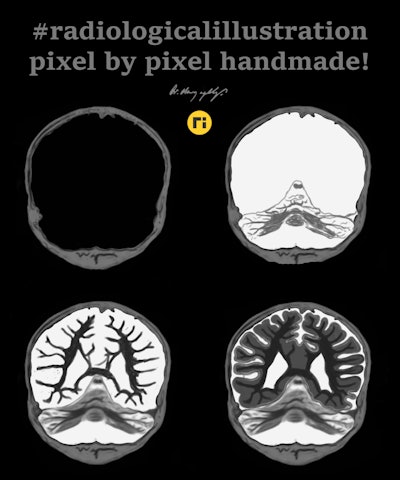

Conceptually, I think it is possible to define the term “radiological illustration” as an emerging discipline that transforms medical imaging data into an aesthetic and didactic narrative. I emphasize that with the motto “pixel by pixel handmade.” I am trying to open a “new path” for the use of visual communication in medical education by trying to combine scientific accuracy in radiological terms with artistic creativity. With this statement, I am trying to express that instead of modifying radiological images, I draw each pixel by hand using technological tools and create a new visual that is both artistically and scientifically original, while remaining faithful to radiological principles.

It’s important to note that radiological illustration should not be confused with medical illustration. The former has yet to be systematically defined in the literature. I believe it deserves recognition as a distinct sub-branch within the broader medical illustration domain.

My presentation on the evening of 20 November will be in Turkish, but most of the images in my slides are from my social media posts. As the saying goes, "a picture is worth a thousand words," so I won't need to talk much! Those who wish can activate the live English translation settings during the presentation, so there will be no obstacle to understanding what I am saying.